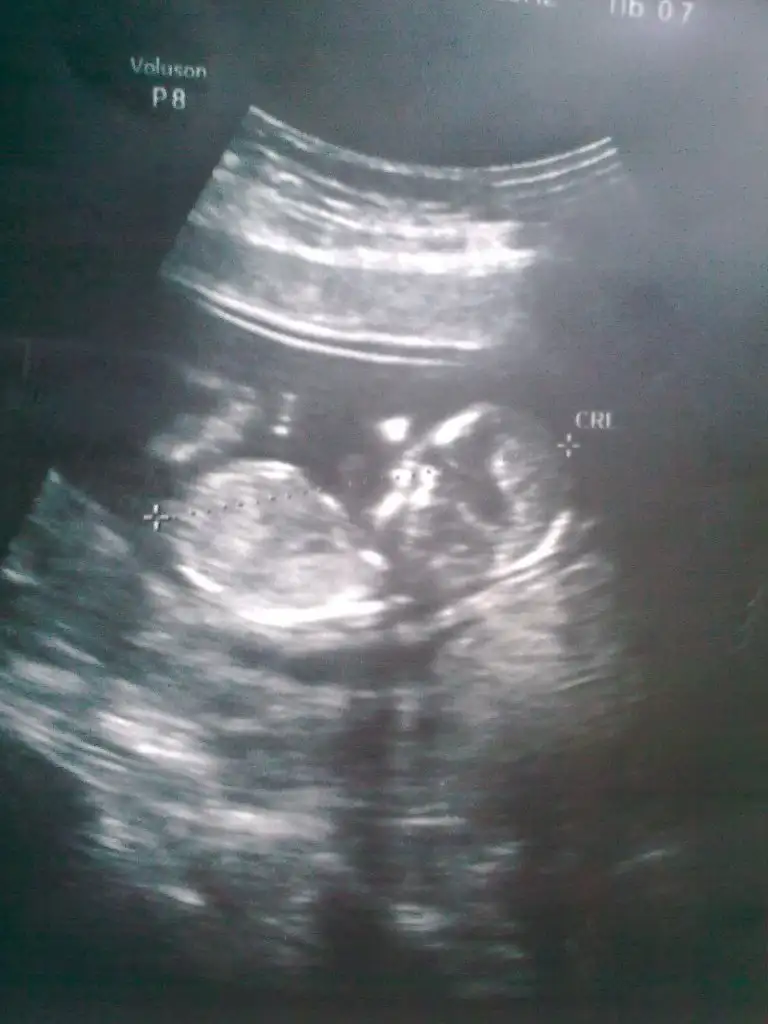

Çıkıntısı gözükmüyo canım ben erkeğe benzettim ama en son resimde paralel bir görüntüde var..Peki sence bizimki ne olabilir:)

Ben bitane resim koydum canım oda bu zatenÇıkıntısı gözükmüyo canım ben erkeğe benzettim ama en son resimde paralel bir görüntüde var..

Canim ben kiz dedim seninkine...bence kiz diyorum...nub u paralel cunku...bariz kendin de gormussun...hayirlisi olsun canimBaksana ben mı yanlıs bakıyorum canm

Canım bazen paraleller Erkeğe dönebiliyordu ama senin yaptığın bu fotoya bakınca bariz kız. Nerdeyse aynısı üstteki resmin :)Canm ben boyle cızdım paralel geldı ama yanlışmı bakıyorum acaba alttakı benım bebıs